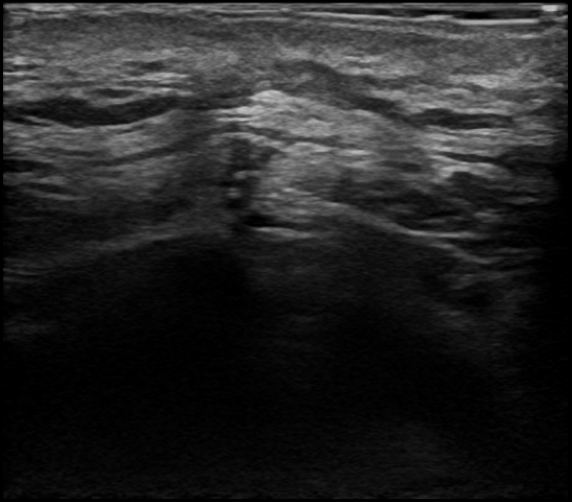

2回目の再発術前

3回目の術後半年後 再発なし